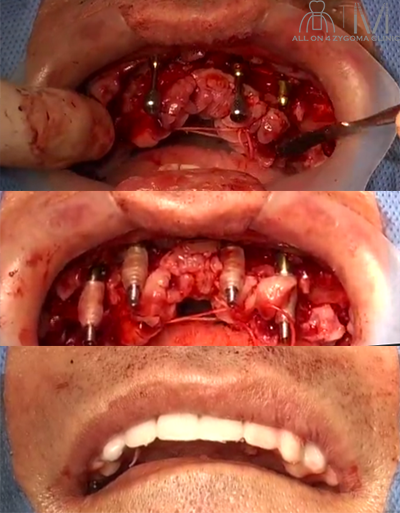

手術所見

2024年5月某日 静脈内鎮静法下に手術施行

術式:静脈内鎮静法下、上下顎オールオン4ザイゴマインプラント

(多数歯抜歯術、ブレードインプラント、撤去、ザイゴマインプラント埋入術)施行

手術時間:2時間56分

術後口腔内所見

術直後の写真。上顎のプロビジョナルレストレーショの52┴25相当部の口蓋側に4つのアクセスホールを認め、オールオン4である事が確認出来る。上顎正中に対し、下顎正中はやや左側に偏位している。